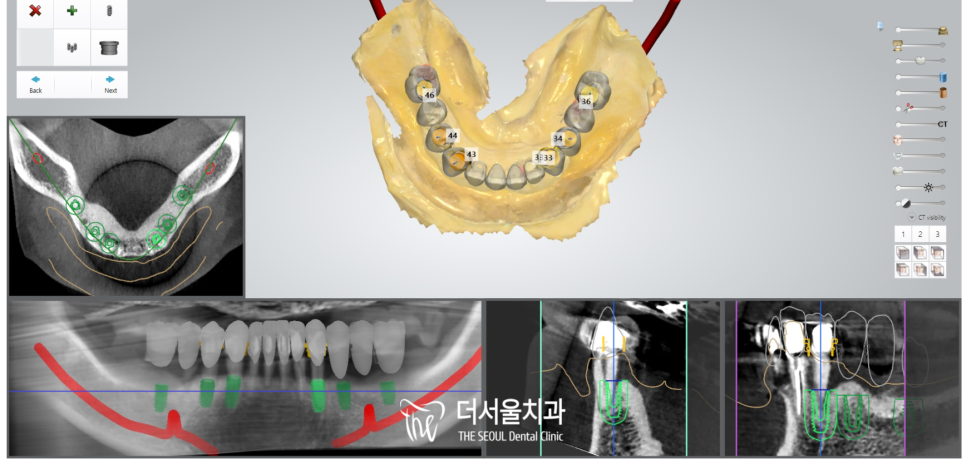

치료 계획을 세우기 전,

정확하게 파악하기 위해 엑스레이를 찍었습니다.

하악 전치부 치아들이 남아있었지만

이곳도 썩 좋지는 않았는데요.

기존에 근관치료를 받았던 밑으로

이차우식 및 염증이 생겨

동요와 치조골 소실이 관찰되었습니다.

따라서 더서울에서는

총 7개의 픽스처를 식립하여

개선을 도와드리기로 했습니다.

『네비게이션 임플란트 : 편안하고 정확한 식립!』

디지털 분석을 통해

환자의 구강에 맞는 맞춤 계획을 세웠습니다.

최종 보철 제작까지 미리 고려하여

픽스처의 방향, 각도를 설정해 주었습니다.